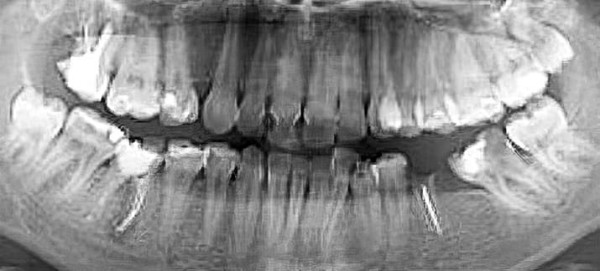

Специалист рассказал о стадиях формирования 8-х зубов, которые всегда следует учитывать при принятии решения об их удалении (см. рис. 1.): А — зачаток зуба, кальцификации нет, В — начальная кальцификация бугров, С — кальцификация бугров, D — начало кальцификации коронки, Е — полная кальцификация коронки, F — начало формирования корней, G — полное формирование корней, H — закрытие верхушечных отверстий корней.

Рисунок 1. Стадии формирования 8-х зубов по данным ортопантомографии.